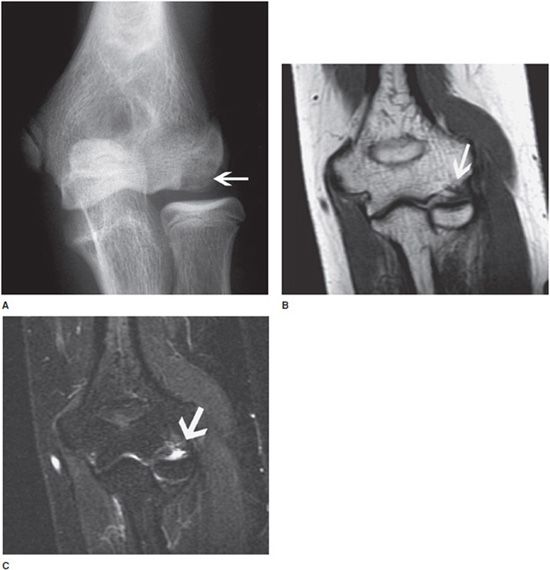

From radiologykey.com